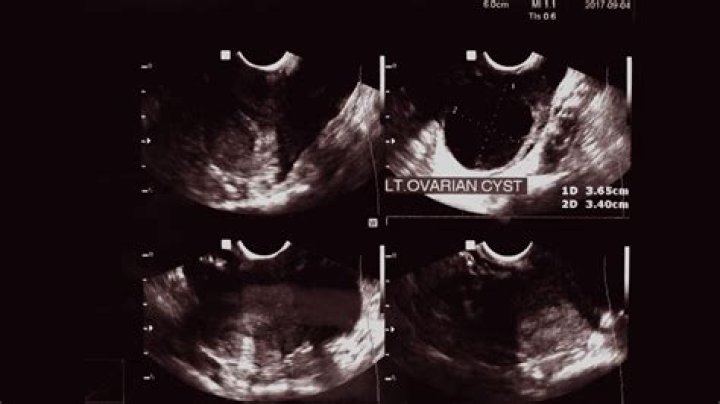

Is a 4 cm ovarian cyst big?

A simple cyst is a round or oval anechoic fluid collection with smooth thin walls, no solid component or septation, and no internal flow by using color Doppler imaging (Fig 1). When describing cysts in the pelvis, we use the term adnexal if the cyst is not clearly arising from the ovary.

Adnexal masses are characterized on ultrasonography as cystic, solid, or complex. According to an American College of Radiology guideline, simple cysts in premenopausal women are considered benign. 11 Complex masses may rarely be malignant in premenopausal women.